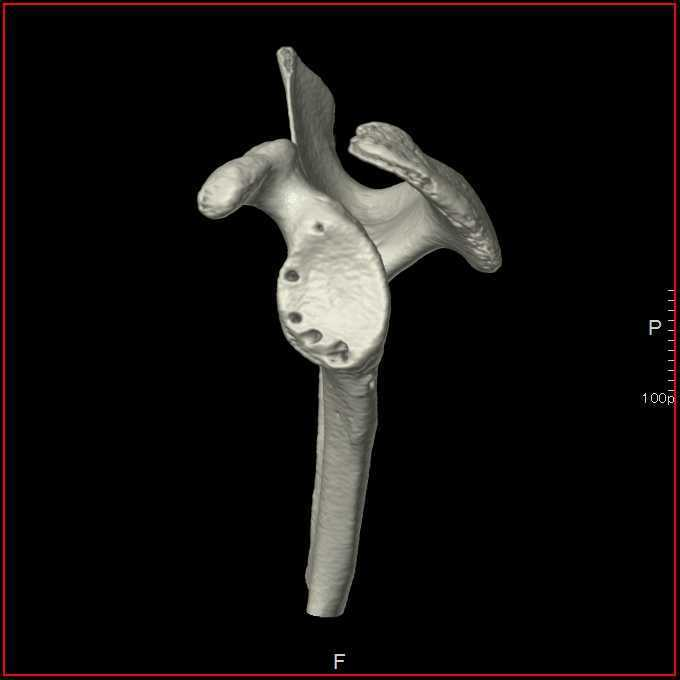

脱臼を繰り返すとどうなるか

脱臼を繰り返すと、前方を支える軟部組織(関節唇、関節包)がさらに損傷していき、最終的には受け皿の骨(肩甲骨)が欠けて小さくなったり、上腕骨の後方に大きな骨欠損が生じたりします。その結果、スポーツ活動はもちろん、日常生活にも大きな影響が出て生活の質(QOL)が著しく低下してしまいます。

特に 若年者や接触スポーツを行う方、骨欠損がある場合は再発リスクが非常に高い ため、早期に正しい治療を受けることが非常に重要です。

関節窩骨欠損がある場合の手術法

AGR(鏡視下バンカート修復術+腸骨移植)

骨盤(腸骨)から骨を採取して、欠損した肩甲骨の関節窩にブロックを用いて移植します。その後、鏡視下バンカート修復術を行います。